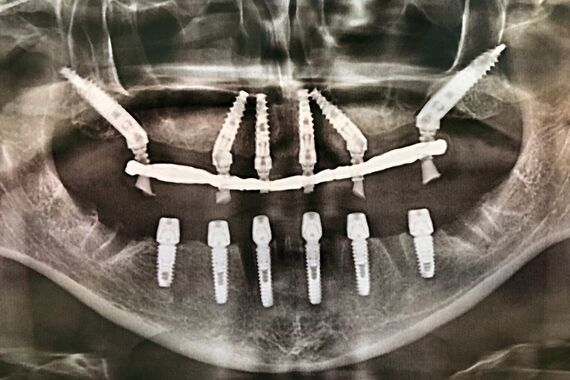

Изучив данные 3D-исследования, которые пациентка прислала через интернет, доктор предложил провести протезирование верхней и нижней челюстей в кратчайшие сроки при помощи методики All-on-6 (все на 6-ти). Во время операции были удалены старые протезы, оставшиеся зубы, установлены 6 имплантатов на верхней и 6 имплантатов на нижних челюстях, и за 5 дней были изготовлены и фиксированы несъемные эстетичные протезы на обеих челюстях.